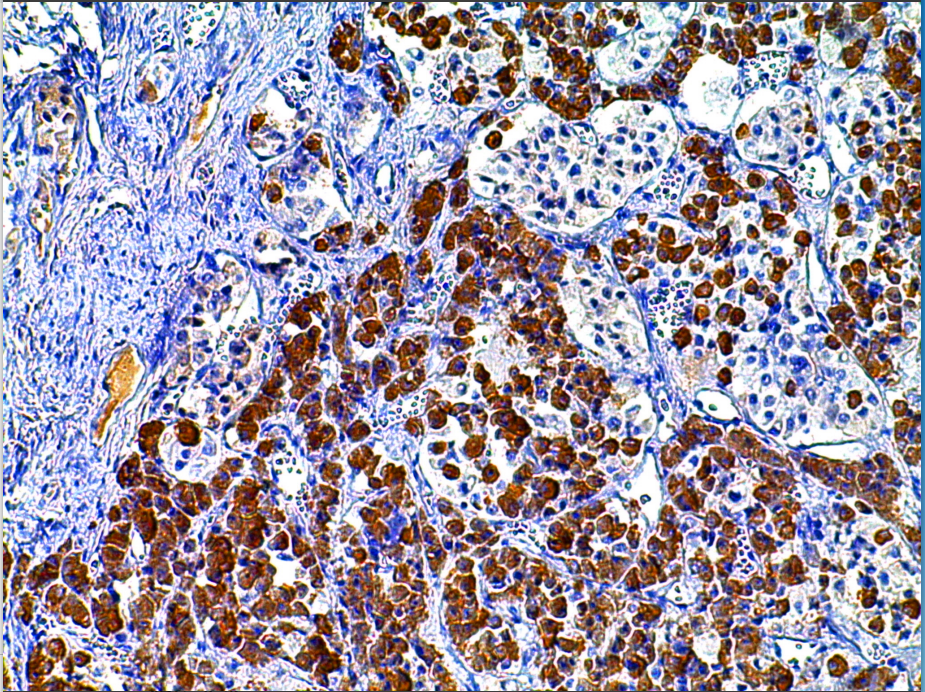

Cellular localization: cytoplasm

Positive control: Pituitary gland

Growth hormone is a hormone synthesized and secreted by growth hormone cells in the anterior lobe of the pituitary gland. It can promote protein synthesis and bone development. This antibody can react with human GH and has a weak cross-reaction with hormones such as prolactin, TSH, LH and FSH. It is mainly used in the research of functional classification of pituitary adenomas.

Human Growth Hormone antibody reagents can specifically bind to Human Growth Hormone molecular antigens. Immunohistochemical kits containing Human Growth Hormone antibody reagents are suitable for the auxiliary diagnosis of growth hormone deficiency or resistance syndrome.